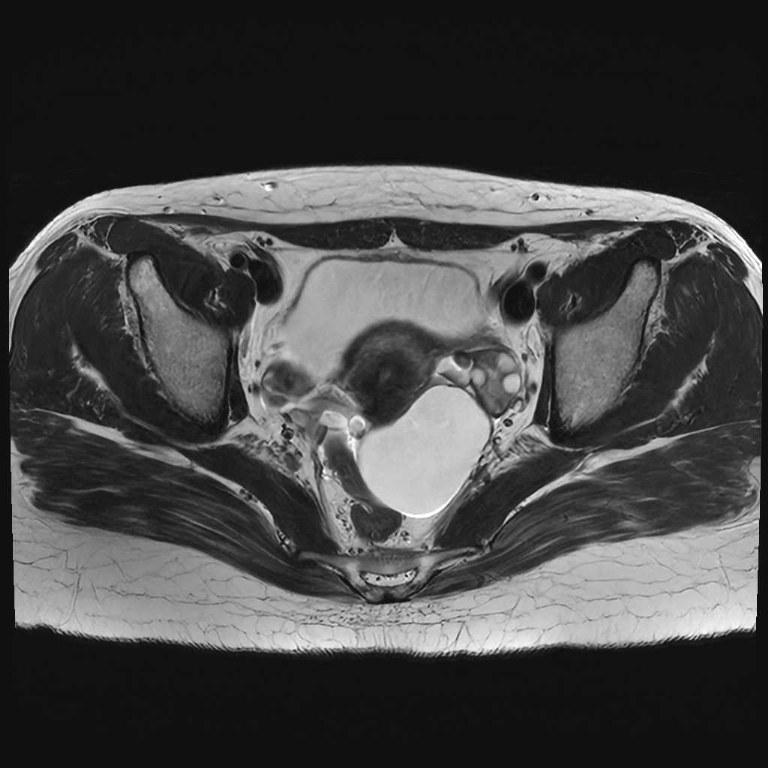

婦人科領域

子宮卵巣

子宮筋腫

卵巣嚢腫